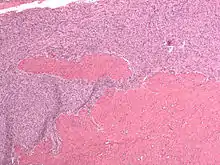

| Micrograph of a low-grade endometrial stromal sarcoma. H&E stain. | |

Low-grade endometrial stromal sarcoma consists of cells resembling normal proliferative phase endometrium, but with infiltration or vascular invasion. These behave less[3] aggressively, sometimes metastasizing, with cancer stage the best predictor of survival. The cells express estrogen/progesterone-receptors.

- Monotonous ovoid cells to spindly cells with minimal cytoplasm.

- Prominent arterioles. Angiolymphatic invasion common.

- Up to 10-15 mitotic figures per 10 HPF in most active areas.

- Tongue-like infiltration between muscle bundles of myometrium.